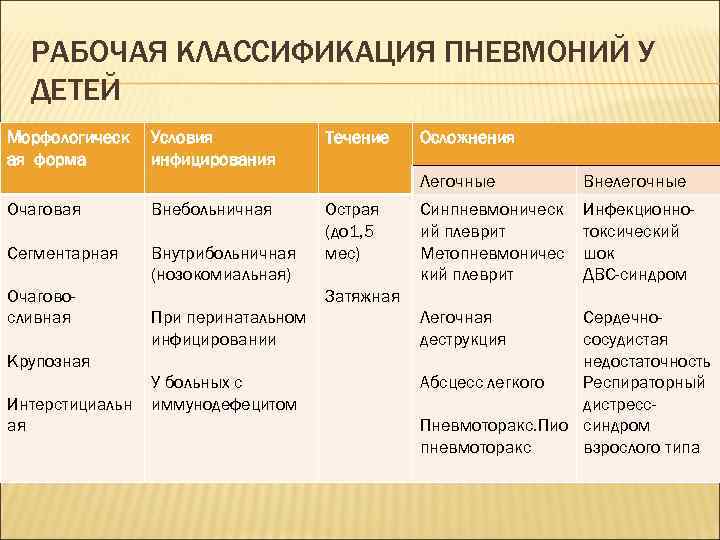

РАБОЧАЯ КЛАССИФИКАЦИЯ ПНЕВМОНИЙ У ДЕТЕЙ Морфологическ ая форма Условия инфицирования Течение Осложнения Легочные Очаговая Внебольничная Сегментарная Внутрибольничная (нозокомиальная) Очаговосливная Синпневмоническ ий плеврит Метопневмоничес кий плеврит Инфекционнотоксический шок ДВС-синдром Затяжная При перинатальном инфицировании Крупозная Интерстициальн ая Острая (до 1, 5 мес) Внелегочные У больных с иммунодефецитом Легочная деструкция Сердечнососудистая недостаточность Абсцесс легкого Респираторный дистресс. Пневмоторакс. Пио синдром пневмоторакс взрослого типа